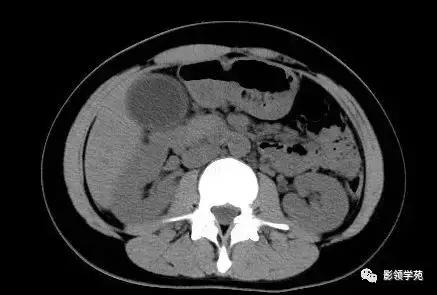

急性坏死型胰腺炎:CT平扫,胰腺密度不均匀减低,胰腺边界模糊,胰腺周围较多渗出积液,肝周可见积液。